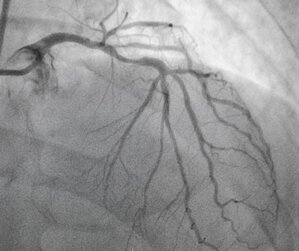

Angiography | Dr. Ishwar Zanwar

Angiography Angiography is a medical imaging technique used to visualize blood vessels in the body, particularly in the heart and the brain. It is ...

Read More about Angiography | Dr. Ishwar Zanwar